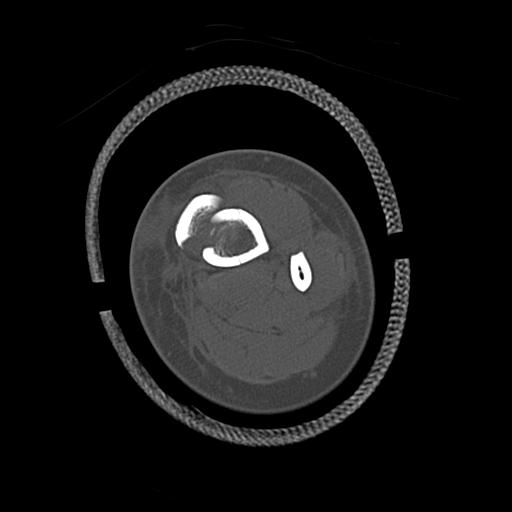

49554 3/13 膝 4R 3/16 4R 1/18 2R 78歳男性 膝蓋骨骨折